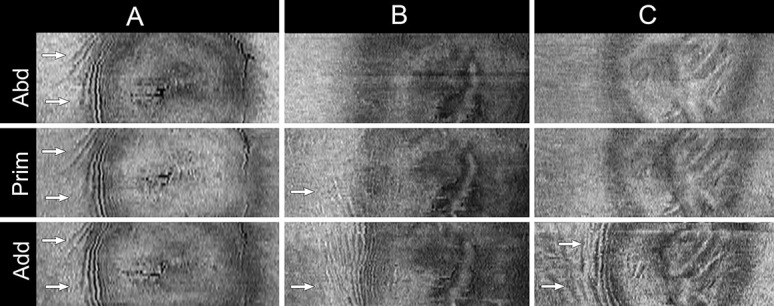

The mechanical forces on the ONH induced by ocular ductions can also affect the pattern and distribution of PPW (105). As force increases, the amplitude and the area of the folds increase, and thus PPW located temporally become more evident when the eye is adducted 30° (Fig. 15B). Sometimes, folds that are absent in primary position are only visible in adduction, particularly with large tilt angles (Fig. 15C). This does not seem to be the case in normal subjects and ODD with mild elevation (105). Examining the eye in adduction increases the sensitivity of detecting folds that may help to differentiate papilledema from pseudopapilledema. Large disparities in shape between primary position and adduction, that is, with large tilt angles (Fig. 14B) can also be a sign of intracranial hypertension and optic nerve sheath meningiomas.

FIG. 15.

En face optical coherence tomographies at the vitreoretinal interface obtained in primary position (prim), 30° abduction (abd), and 30° adduction (add). Three patterns are displayed. A. Peripapillary wrinkles (PPW) in primary position that are not affected by changes in eye position; (B) PPW in primary that become more evident in adduction and absent in abduction; (C) an example of PPW that are absent in primary and visible only when the eye is adducted. The white arrows in each case highlight the area of folds temporal to the optic disc.